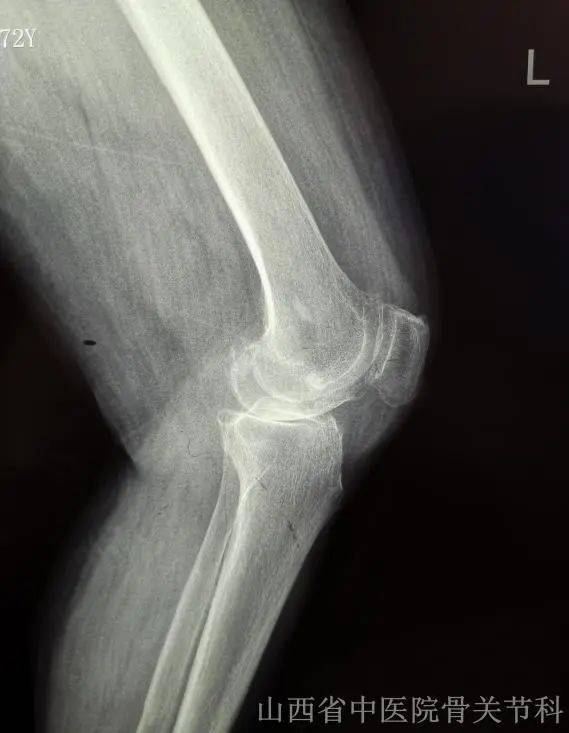

骨关节炎通常累及全身关节,以膝关节最为常见,病理表现为关节软骨的渐进性破坏、软骨下骨硬化和骨赘形成等,临床症状表现为疼痛、关节僵硬、关节活动度显著降低,甚至诱发残疾,其具体的发病机制目前尚未完全明确,是老年人致残的首要原因。

3.关节肿胀和畸形

双手常出现指间关节骨性膨大和畸形,还有膝关节肿胀、内外翻畸形等。